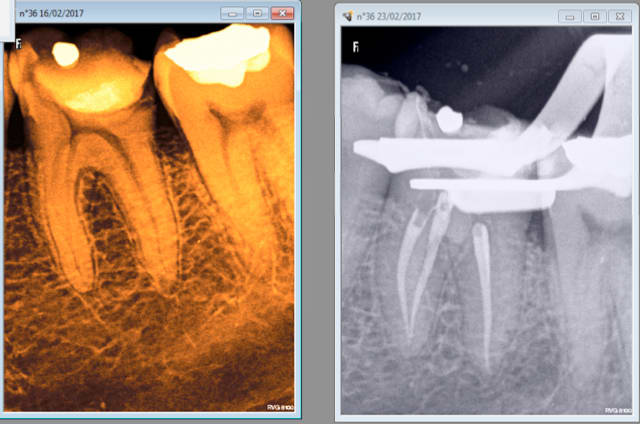

23/02/2017 à 10h26

Endo 36, 30 mn. Mais c'est opérateur dépendant. -))))

Capture d écran 2017 02 23 10.26 - Eugenol